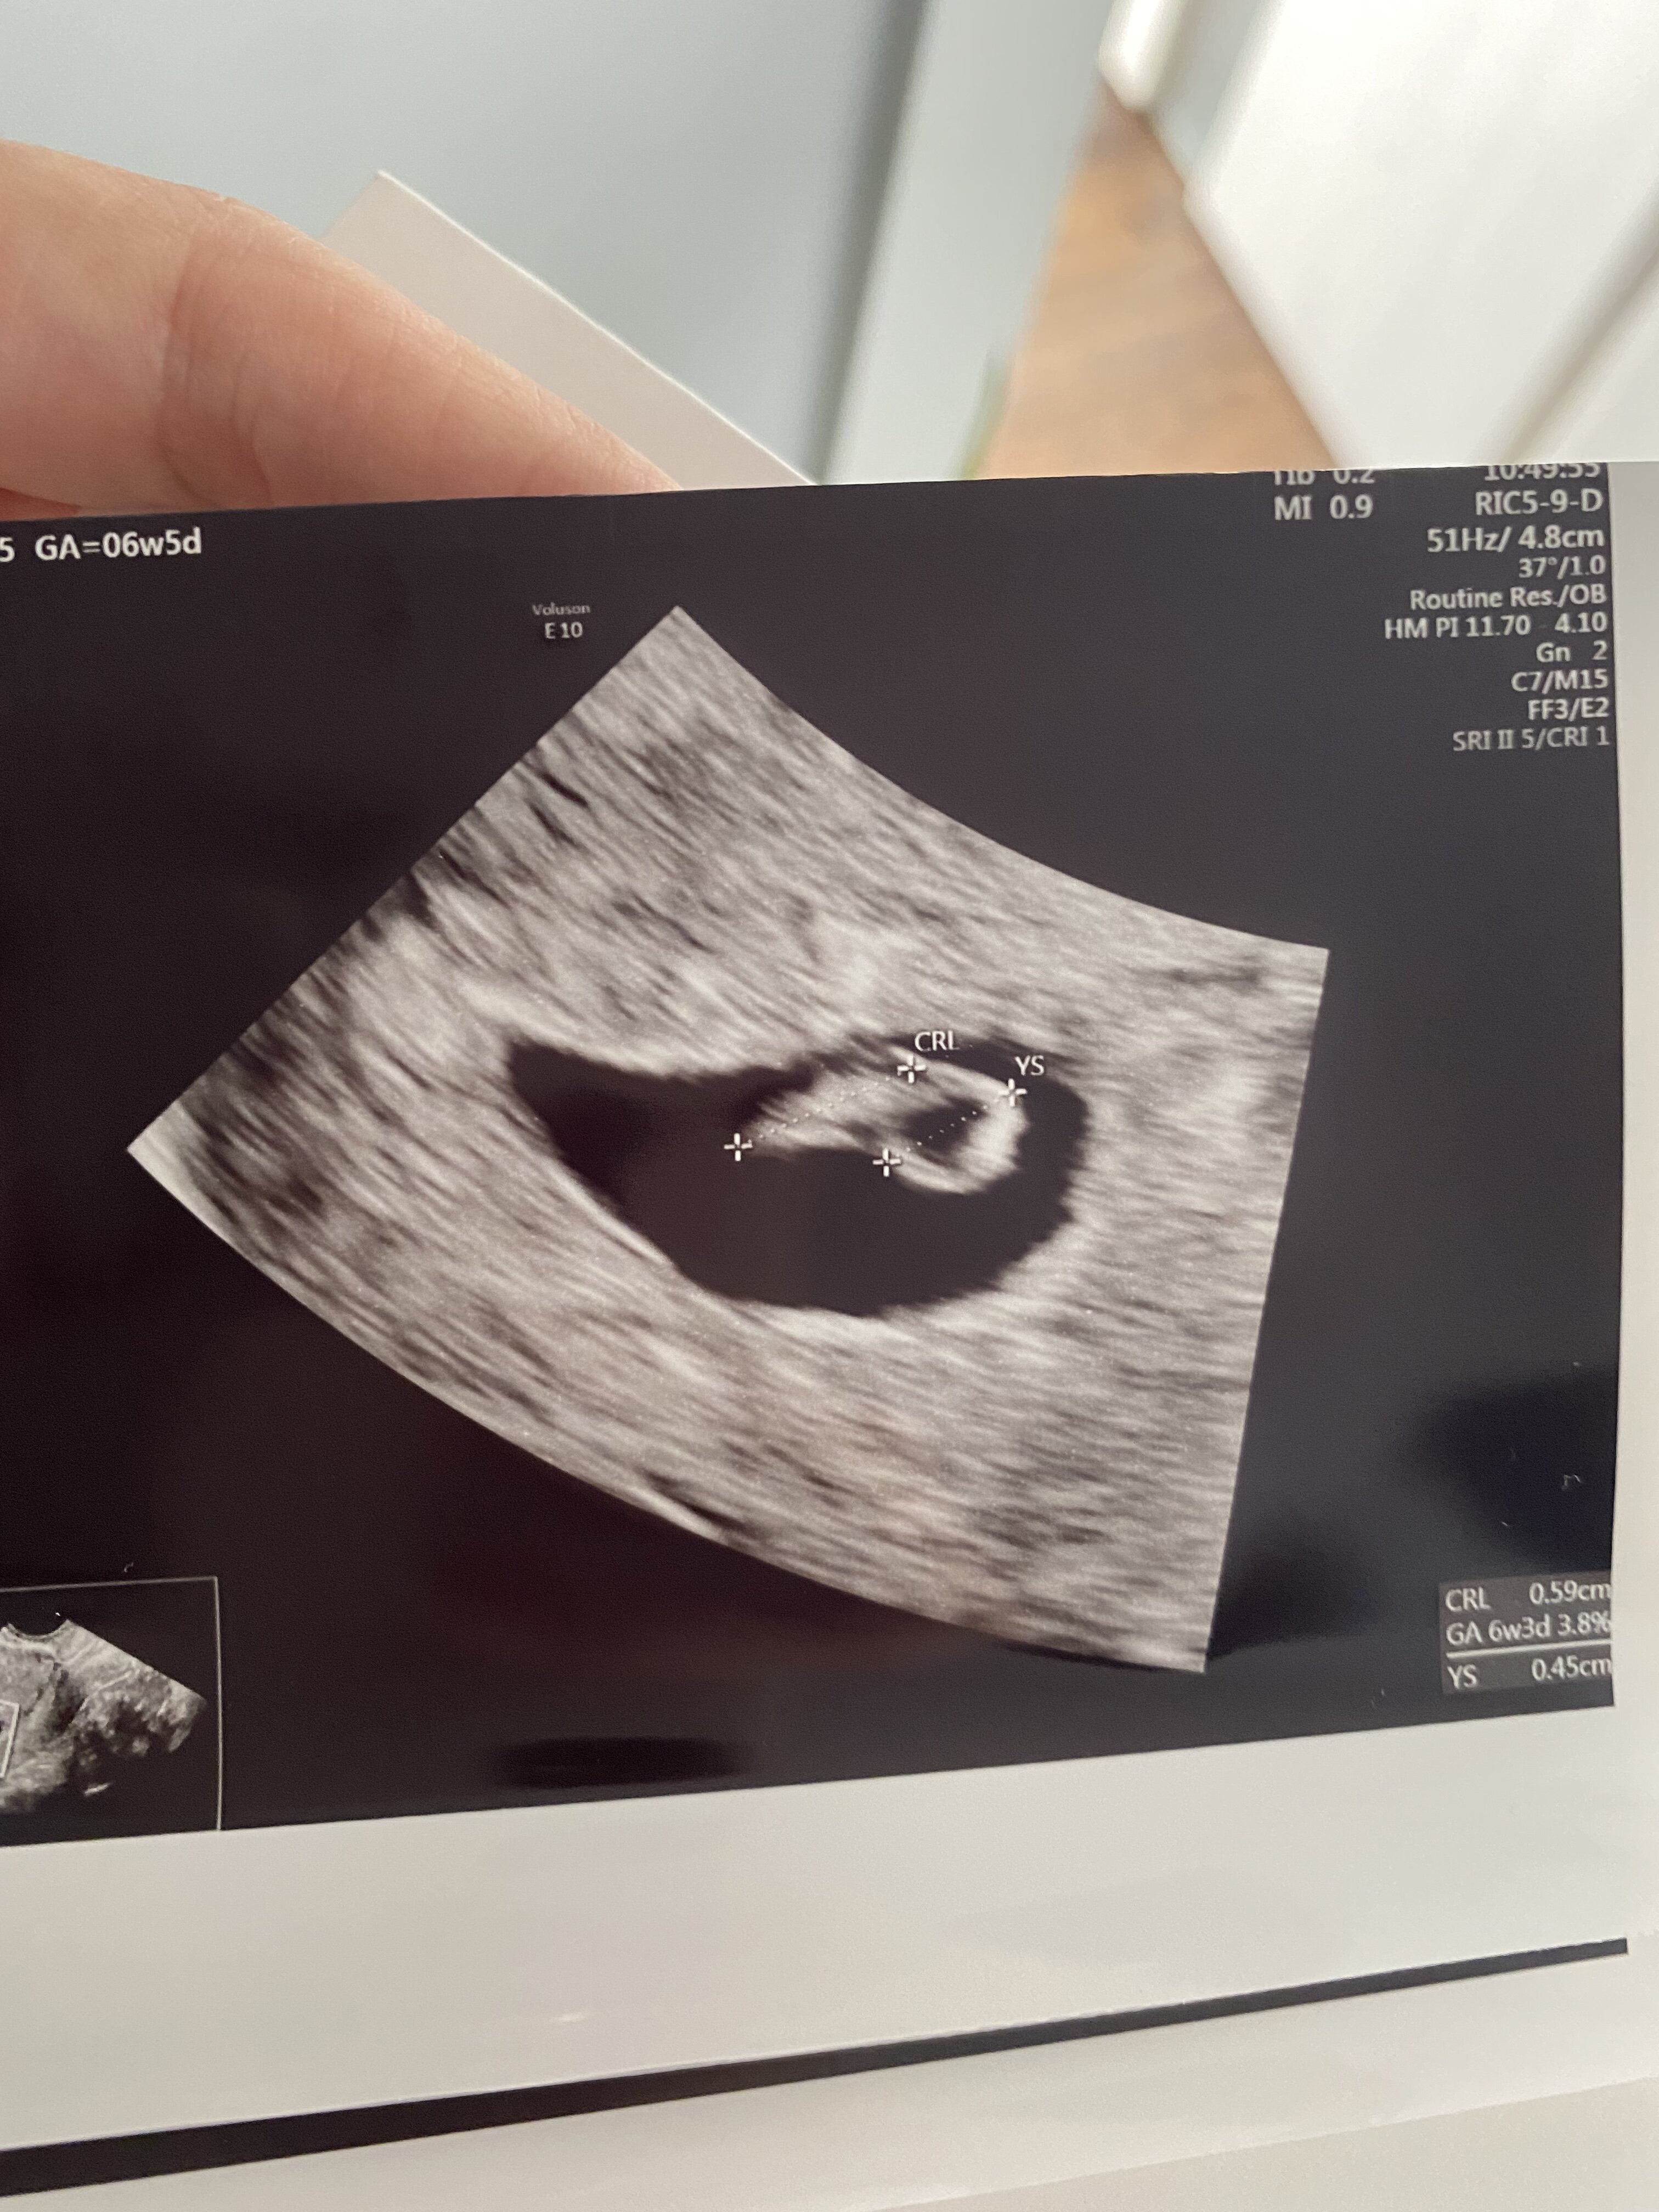

Jets serduszko![]()

Wiek ciąży z usg zgadza sie z terminem z OM. Termin porodu 15.05![]()

Od razu zauważyłam pikający punkcik, który boje z prędkością 124/min.